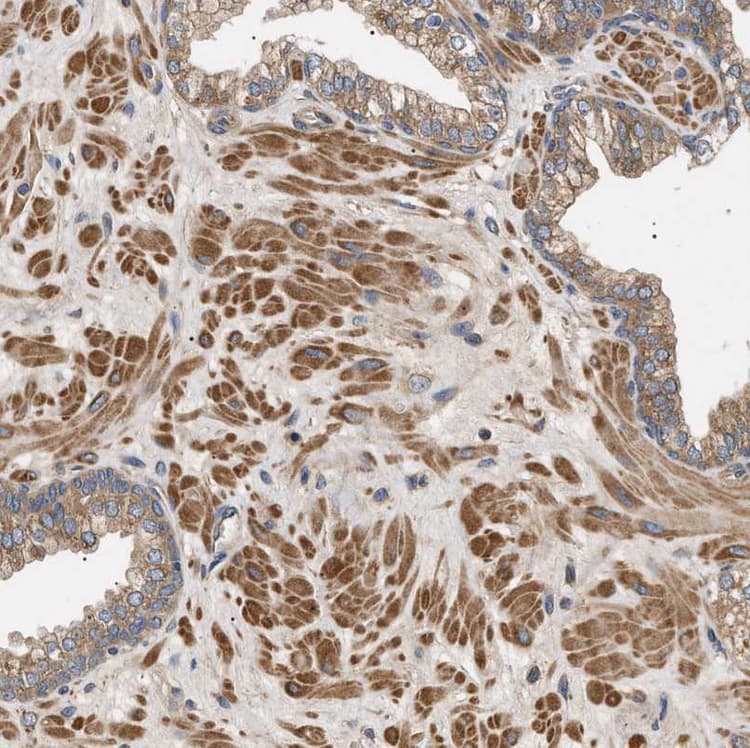

Rabbit Polyclonal PPM1B antibody. Suitable for IHC-P, WB, ICC/IF and reacts with Human samples. Cited in 1 publication. Immunogen corresponding to Recombinant Fragment Protein within Human Protein phosphatase 1B aa 350 to C-terminus.

Applications ICC/IF, IHC-P, WB

Species Reactivity Human